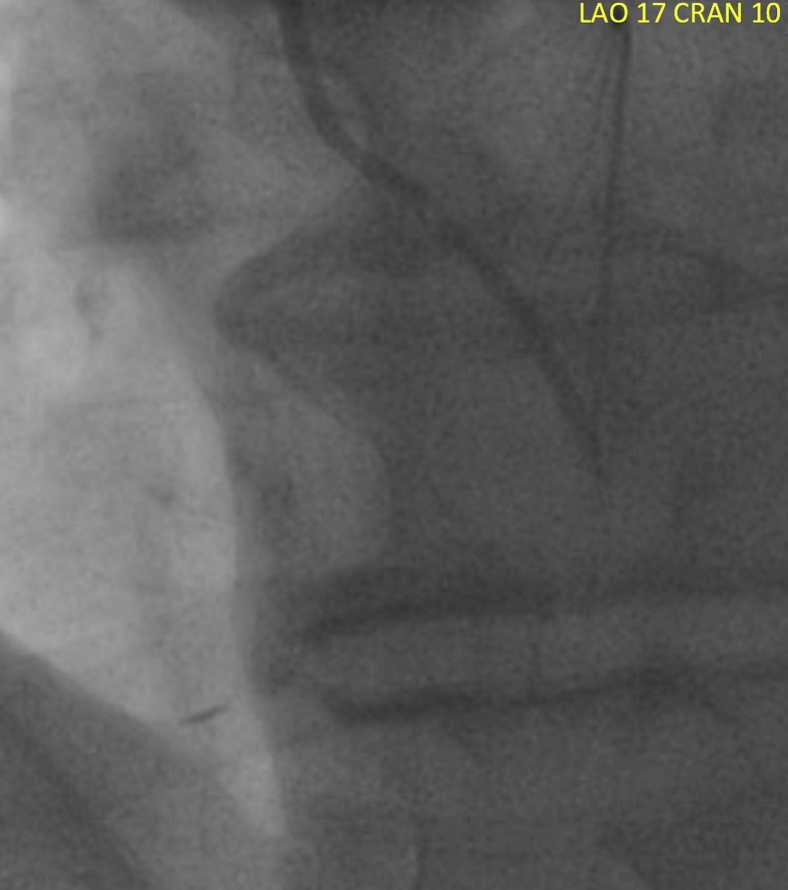

Figure 2.

Completion angiogram, left anterior oblique 17 cranial 10 projection, after robotic-assisted left internal mammary artery to left anterior descending demonstrating poor flow distally, despite intracoronary nitroglycerin. Some retrograde filling of the septal and diagonal branches is seen.

Completion angiogram, LAO 17 cranial 10 projection magnified 2× for comparison, after robotic-assisted LIMA-LAD demonstrating poor flow distally, despite intracoronary nitroglycerin. Some retrograde filling of the septal and diagonal branches is seen. Video available at: https://www.jtcvs.org/article/S2666-2507(20)30198-X/fulltext.